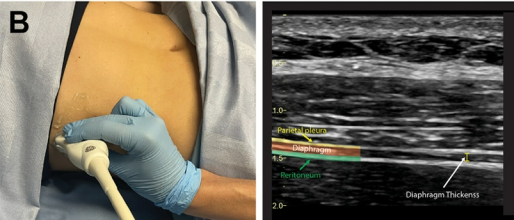

3.2  膈肌厚度及增厚率

1)测量方法:患者取平卧位或半卧位,平静呼吸时测量;线性高频探头,10 Hz,置于腋中线或腋前线8~11肋间,垂直于胸壁皮肤,探头Mark点向上,从头侧向尾侧滑动,吸气相及呼气相膈肌厚度,胸膜内壁及腹膜内壁之间,测量3个呼吸周期,取平均值。膈肌增厚率(TFdi)=(吸气厚度-呼气厚度)/呼气厚度×100%。

需要明确的是,如图3所示,膈肌以橙色标识,胸膜为黄色,腹膜为绿色。测量时需注意:应选取胸膜与腹膜之间的内径作为测量对象,避免将两层膜的厚度计入测量值(否则会导致结果偏差)。操作上需重复测量三次,最终取其平均值以保证数据的准确性。

3  膈肌厚度测量

图源:Crit Care Clin, 2025, 41(3):541-553.